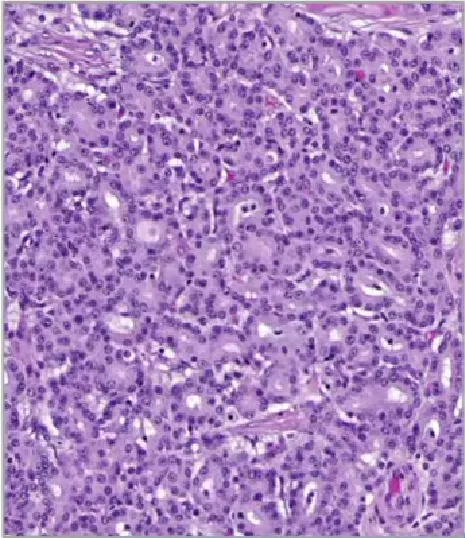

低级别管状腺癌(Low-grade tubuloglandular adenocarcinom)

• 较罕见,且几乎仅发生于炎症性肠病患者

• 分化良好的腺体杂乱无章浸润性生长,且无促结缔组织增生

• 可能起源于低级别常规异型增生或非常规的结肠炎相关异型增生,且有时会表达CK7;

• IDH1突变较为常见

• 预后良好,少数病例会发展为高级别形态。